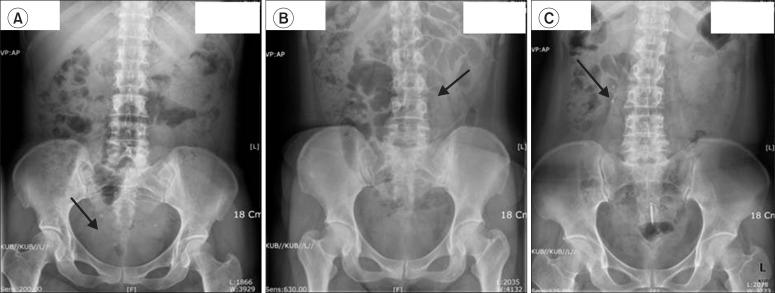

A total of 223 patients treated by ESWL for radio-opaque ureteral stones of 5 to 20 mm were included in this retrospective study. All patients underwent routine blood and urine analyses, plain radiography (KUB), and noncontrast computed tomography (NCCT) before ESWL. Demographic, stone, and radiological characteristics on KUB and NCCT were analyzed. The patients were categorized into two groups: lower-density (LD) group (radiodensity less than or equal to that of the 12th rib, n=163) and higher-density (HD) group (radiodensity greater than that of the 12th rib, n=60). Stone-free status was assessed by KUB every week after ESWL. A successful outcome was defined as stone free within 1 month after ESWL.

本回顾性研究纳入了223例接受ESWL治疗的5至20mm不透X线输尿管结石患者。所有患者在ESWL治疗前均接受了常规血液和尿液分析、腹部平片(KUB)及非增强计算机断层扫描(NCCT)。分析了KUB和NCCT上的人口统计学、结石及影像学特征。患者被分为两组:低密度(LD)组(放射密度小于或等于第12肋,n = 163)和高密度(HD)组(放射密度大于第12肋,n = 60)。ESWL治疗后每周通过KUB评估结石清除情况。成功的定义为ESWL治疗后1个月内结石清除。